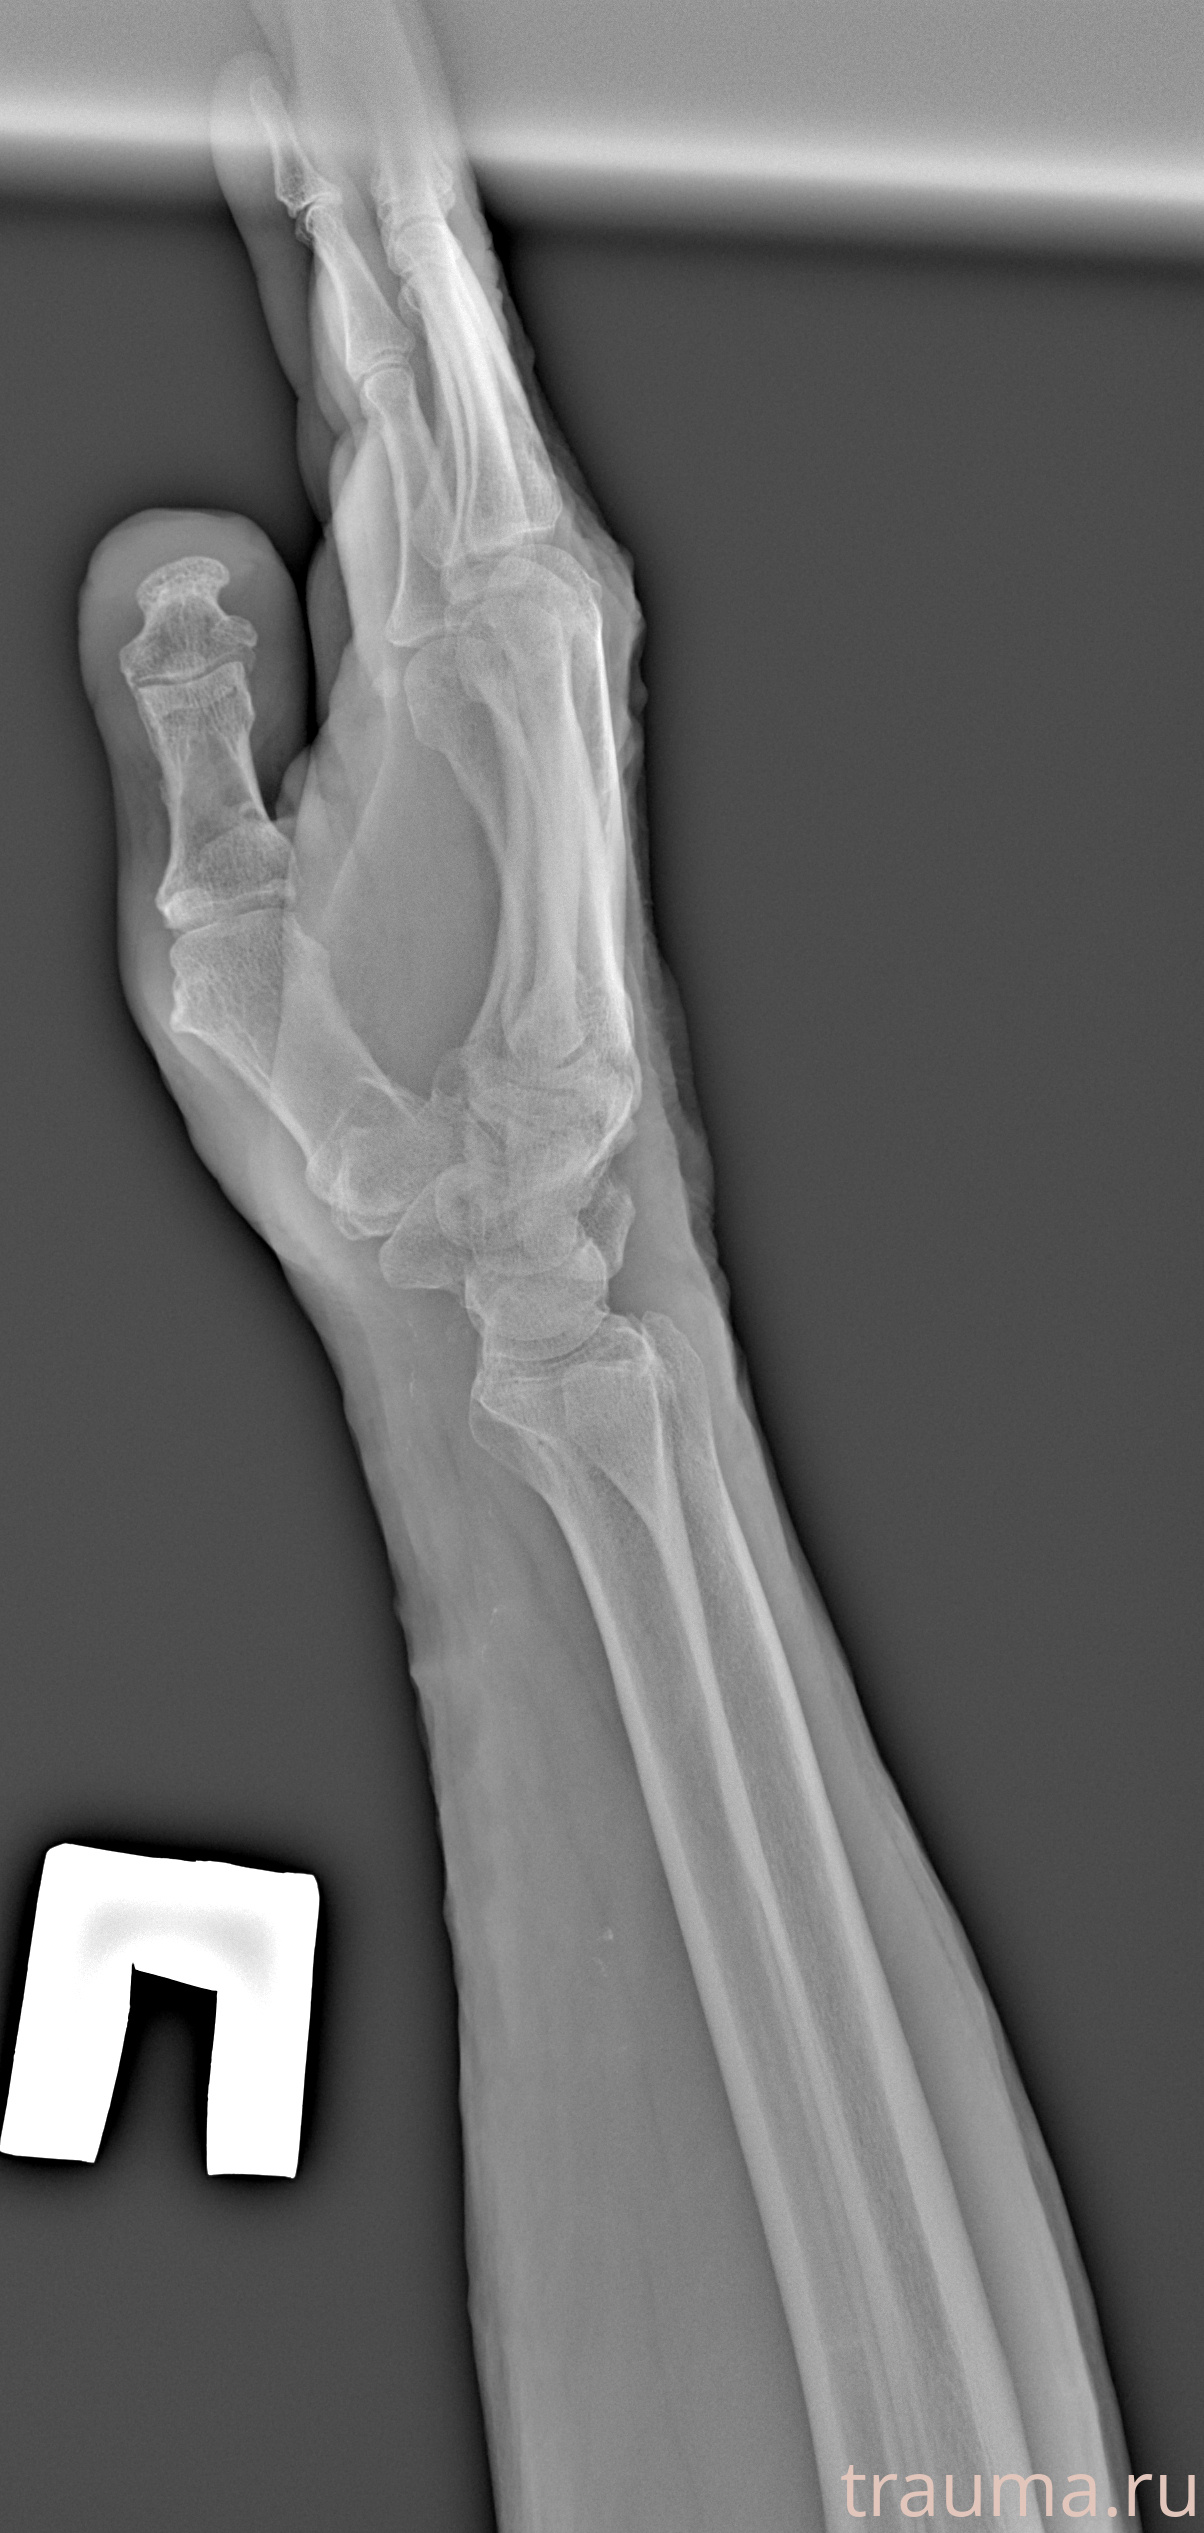

Рентгенограммы

Рентген на дому: по вашему адресу приезжает врач-рентгенолог, травматолог-ортопед с мобильным рентгеновским аппаратом, проводит диагностику травмы или заболевания, делает необходимые рентгенограммы, дает рекомендации по дальнейшему лечению. Получить качественные снимки в домашних условиях возможно благодаря уникальной методике, разработанной МосРентген Центром для института  Склифосовского